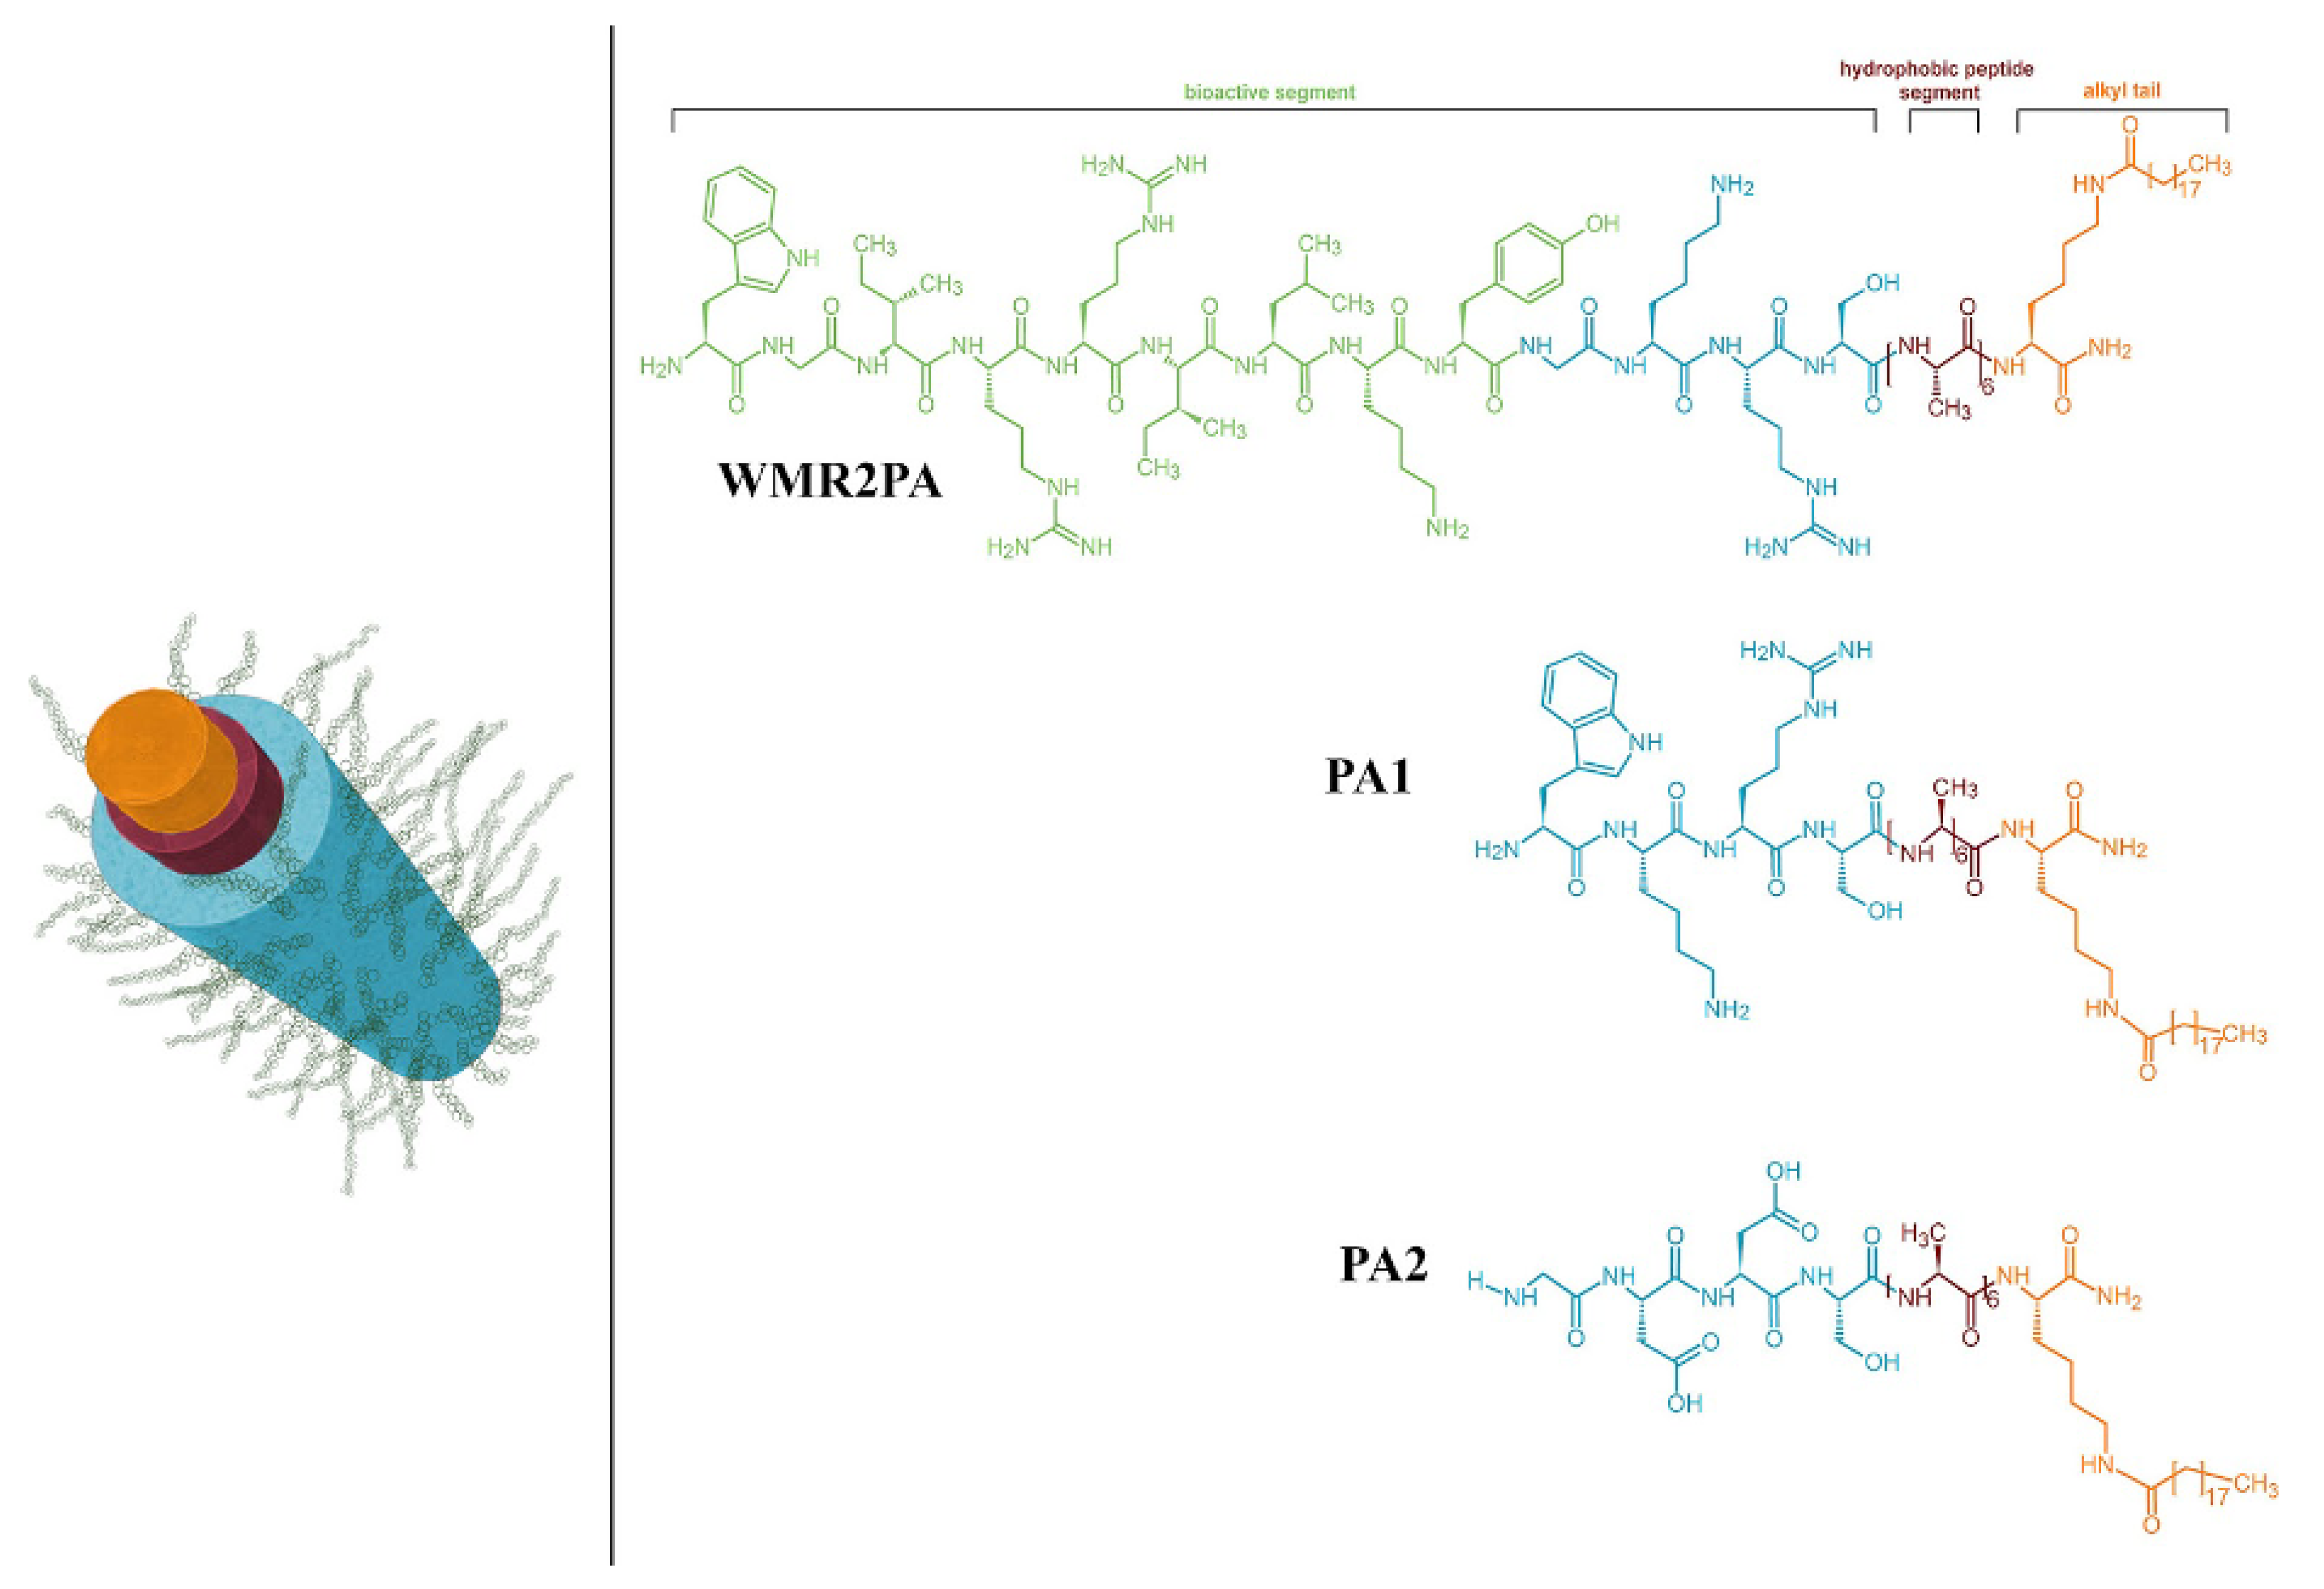

4. Recent Formulations for Antimicrobial Peptides